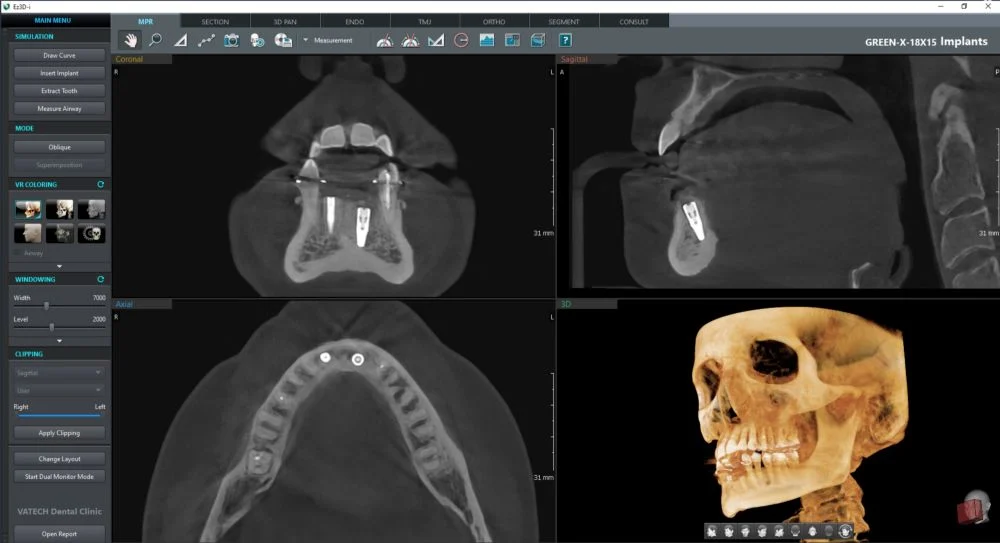

W naszej pracowni korzystamy z najnowszego tomografu Vatech Green X (2025). To aparat, który daje bardzo dokładny obraz, a jednocześnie wykorzystuje niską dawkę promieniowania — dlatego jest bezpieczny także dla dzieci i osób, które muszą wykonywać badania częściej.

- wyraźne obrazy 2D i 3D — pomocne przy implantach, ósemkach, leczeniu kanałowym i ortodoncji

- szybkie skanowanie CBCT — już od 2,9 sekundy

- precyzyjny tryb Endo do diagnostyki kanałów zębowych

Tomografia CBCT tworzy trójwymiarowy obraz zębów, kości, zatok i stawów.

Pozwala na precyzyjne planowanie:

- implantów,

- usuwania ósemek,

- leczenia kanałowego,

- aparatów ortodontycznych,

- diagnostyki bólu zatok i stawu skroniowo-żuchwowego.